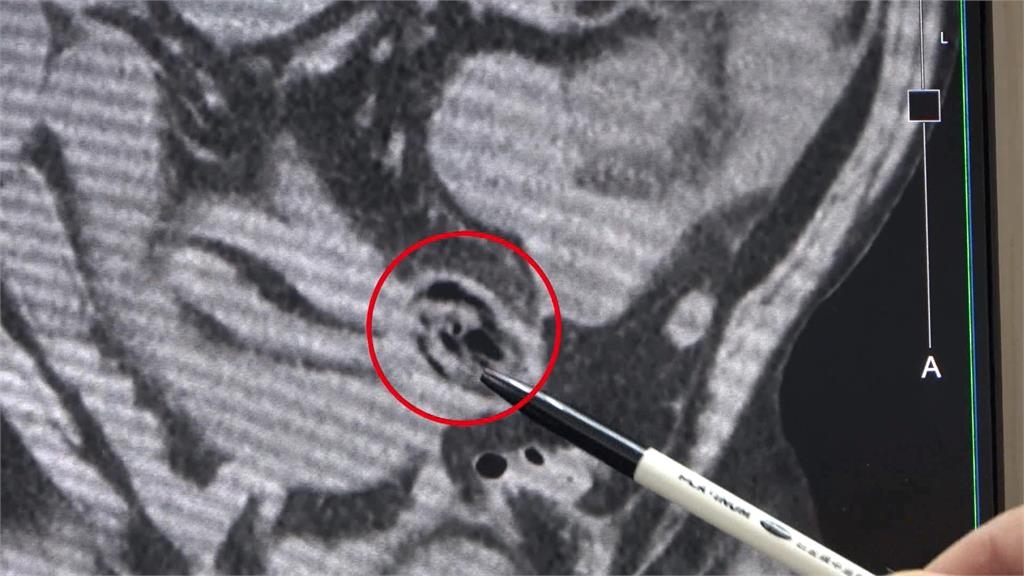

台中有一名患者,因為肚子有脹氣而就診,經過初步檢查,原來是病患的小腸中段,卡住了一個異物,住院四天,都無法自行排出,醫師只好動手術!李綜合醫院外科主治醫師許明賢說明:「他因為吃那口東西,造成腸道狹窄跟阻塞,手術當中,就把腸子剖開把異物取出來。」由於患者腹部之前就動過手術,腸子有沾黏,腸道比較狹窄,加上進食時,食物又沒有充分咀嚼,直接吞下去,以致於發生腸阻塞!李綜合醫院外科主治醫師許明賢說明:「患者四十幾歲,但是全口都沒有牙齒,那可能咀嚼得沒有很完整。」

品嘗一下麻油米糕,上面蓋的是整片冬菇,過年吃桌菜,還有少不了的這款,佛跳牆,大香菇一朵朵!可是,如果像這樣,對半切、直徑大約五公分的香菇,進到了肚子裡,卻過了幾天還一點都沒消化,人恐怕就要吃苦頭了!李綜合醫院外科主治醫師許明賢說明:「這個後來拿出來之後,發現這是一個沒有消化的香菇。」